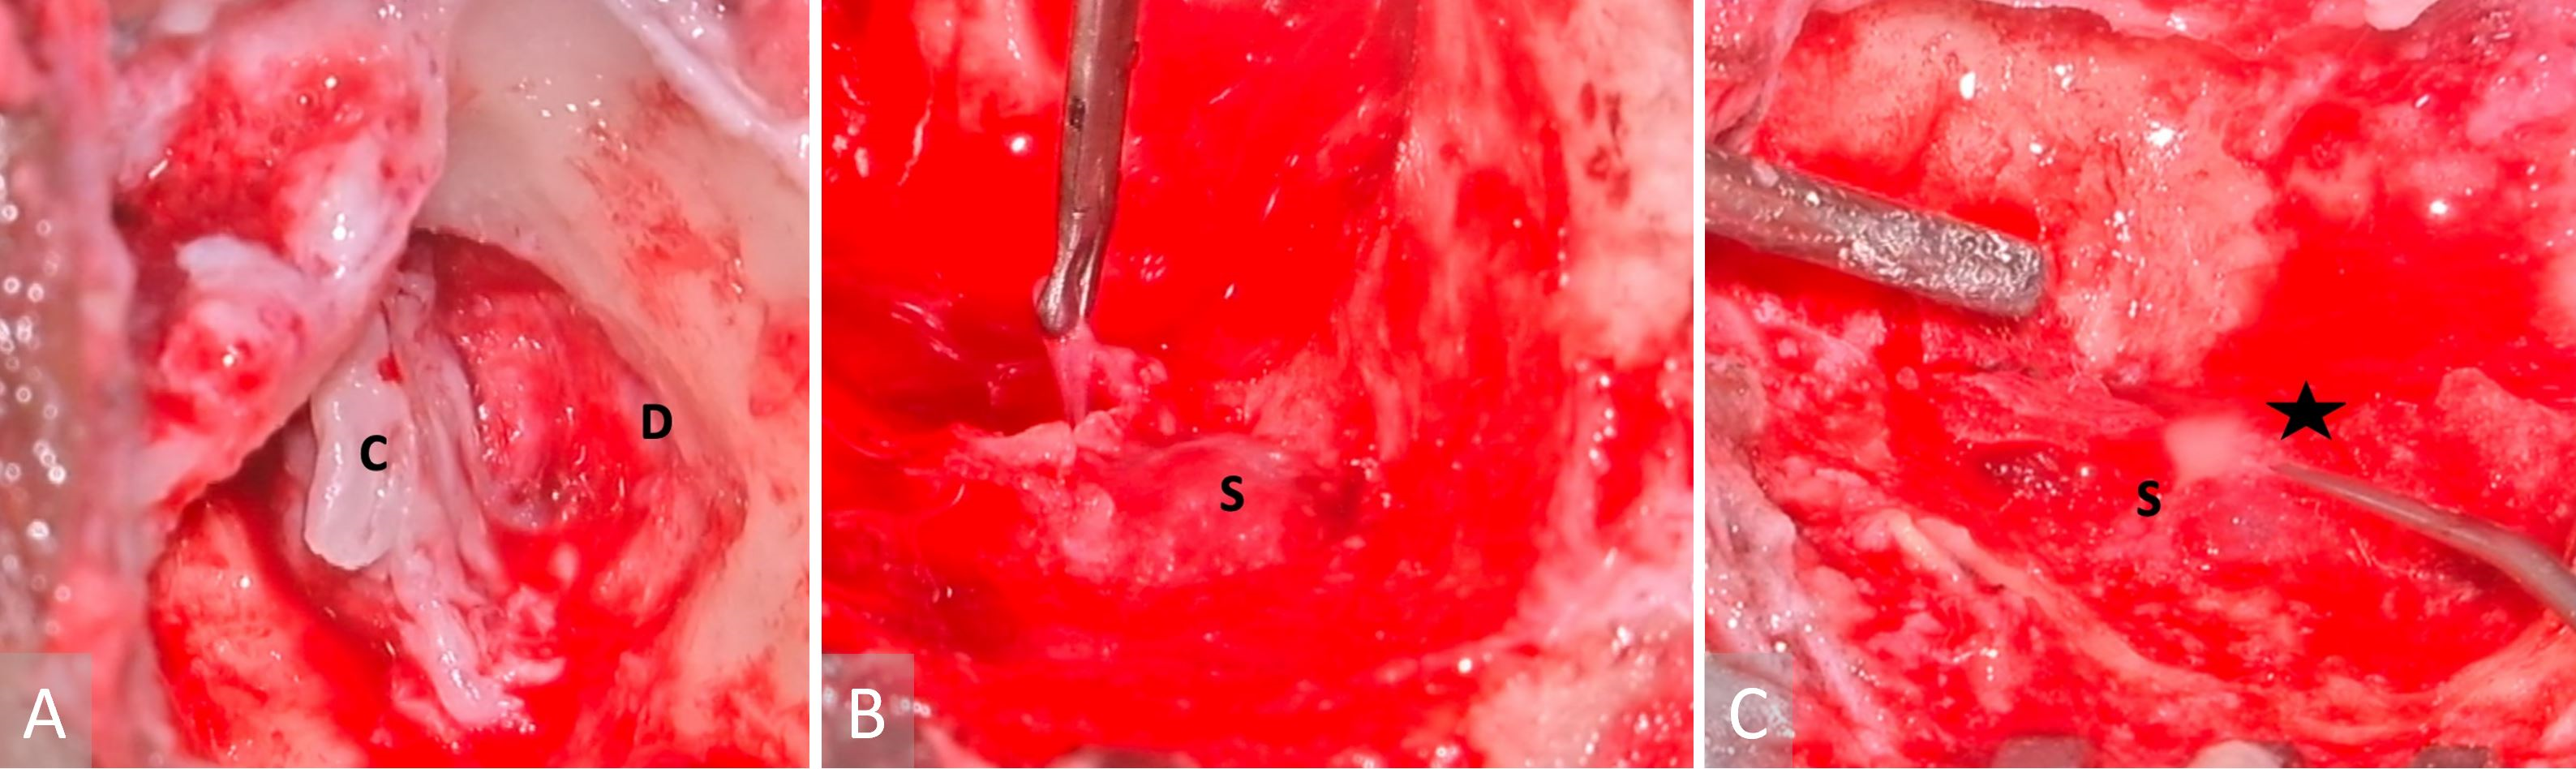

The patient underwent an urgent left modified radical mastoidectomy and meatoplasty. A large middle ear cholesteatoma was discovered intraoperatively, which extended posteriorly into the mastoid antrum (Figure 3A). It was observed that extensive granulation tissue surrounded the suprastructure of the stapes, along with erosion of the malleus head and the incus. The tegmen mastoideum was found to be eroded with a dehiscent mastoid facial nerve segment. Along the course of this nerve, there was a stimulation response of 0.8 mA. The sigmoid sinus plate was extensively eroded by cholesteatoma, with granulation observed on the edematous wall of the sinus (Figure 3B). The thrombus was palpable within the sigmoid sinus, despite pulsations being felt proximally. Purulence was evident in the peri-sigmoid region (Figure 3C).

Figure 3. Images obtained during surgery. (A) A cholesteatoma is present in the left middle ear (labelled with a letter C), as well as a tegmen mastoideum defect and the exposed dura (indicated with a letter D). (B) A sigmoid sinus that has been exposed (marked with a letter S), while granulations have been removed from the peri-sigmoid area. (C) Purulence in the sigmoid sinus (indicated with a letter S) observed during instrumentation of the peri-sigmoid region (marked with a star).